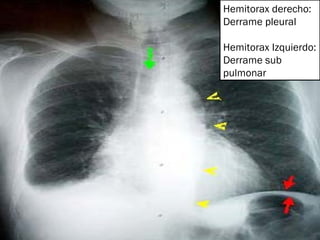

Hemitorax derecho: Derrame pleural Hemitorax Izquierdo: Derrame sub pulmonar

Derrame subpulmonar: Opacificación como velo en hemitorax izquierdo Elevación del hemidiafrágma Desplazamiento de la cúpula gástrica